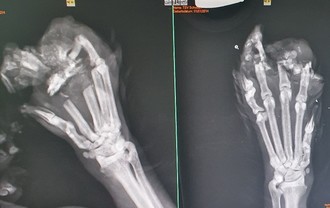

Doch kurz darauf wurde die Freude gedämpft durch einen Anruf mit der Bitte um Hilfe bei einem Katzennotfall in der verlängerten Marienstraße in Schwaan. Vor Ort bot sich den Tierschützern ein entsetzliches Bild eines verletzten zehnjährigen Katers, der nicht wie üblich nachts Zuhause war, sondern sich am Morgen des nächsten Tages unter Schock so nach Hause geschleppt hatte. Sofort wurde der Besitzerin geholfen und der Kater in der Tierarztpraxis Rostock-Sievershagen vorgestellt. Das Röntgenbild offenbarte Schlimmes, beide Vorderpfoten waren zertrümmert und müssten amputiert werden. Der Kater hätte dann nicht mehr laufen können, somit wurde schweren Herzens entschieden, den lieben Mitbewohner der Frau einzuschläfern, um ihm weiteres Leid zu ersparen. Die Röntgenbilder deuten darauf hin, dass die Verletzungen an den Vorder-pfoten mit den geraden Knochenbrüchen von einer Klappfalle verursacht wurden. Die Besitzerin des Katers bekam Hinweise, dass so eine Fallenart gegenüber ihrer Wohnung in einer Gartenanlage am Ende des Wiendorfer Weges an den Bahnschienen verwendet wird.